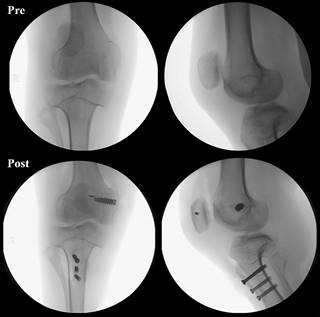

Following the TTO, we conducted an anatomic reconstruction of the medial patellofemoral complex (MPFC) (medial patellofemoral ligament/medial quadriceps tendon femoral ligament-MPFL/MQTFL) using an allograft (semitendinosus tendon) (Figure 4). A small incision was made along the medial border of the patella. With the knee at 30o flexion, a plane was created between the vastus medialis obliquus (VMO) and the joint capsule, extending from the medial patellar edge to the adductor tubercle area, where the femoral insertion of the MPFC is located. A small incision was made at this point, just proximal and posterior to the medial epicondyle, and a guidewire with radioscopic control was positioned. The drill was then used to reach the contralateral femoral cortex, with a drill diameter 1 mm larger than the graft loop. The graft was introduced into the femoral cavity, pulled with a loop in its middle part, and secured with a bioabsorbable interference screw, leaving a shorter and a longer free end available for MPFC reconstruction. Next, a 3.5 mm anchor was placed at the superomedial patellar border, and both graft ends were passed through the plane previously created between the joint capsule and VMO from the femoral insertion. The shorter free end of the graft was secured using anchor sutures in the patella with appropriate tension. The longer end was then passed through a slot in the quadriceps tendon made between transverse layers of the tendon approximately 1.5 cm proximal to the superior border of the patella (Figure 5). Finally, the VMO fascia was closed to provide additional support for reconstruction.